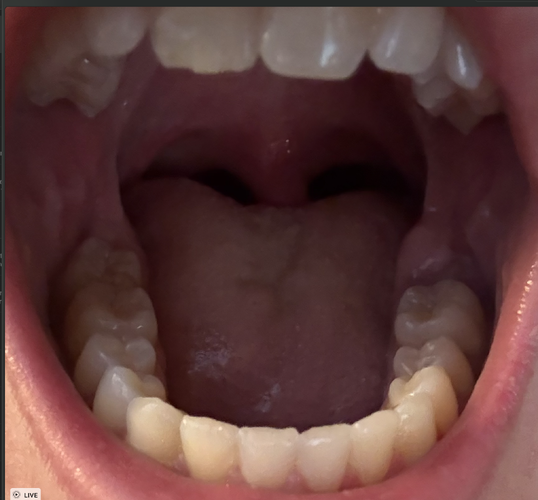

Would you rather do custom armless MARPE from a local airway/TMJ ortho for 5-7k - Jit is kinda popular in the Ortho sphere and only 30 min drive

or drive almost 3 hours to Dr Newaz for FME at 20-30k?

Typical retard asymmetries where one side sits slightly lower (brow, orbital, cheekbone).